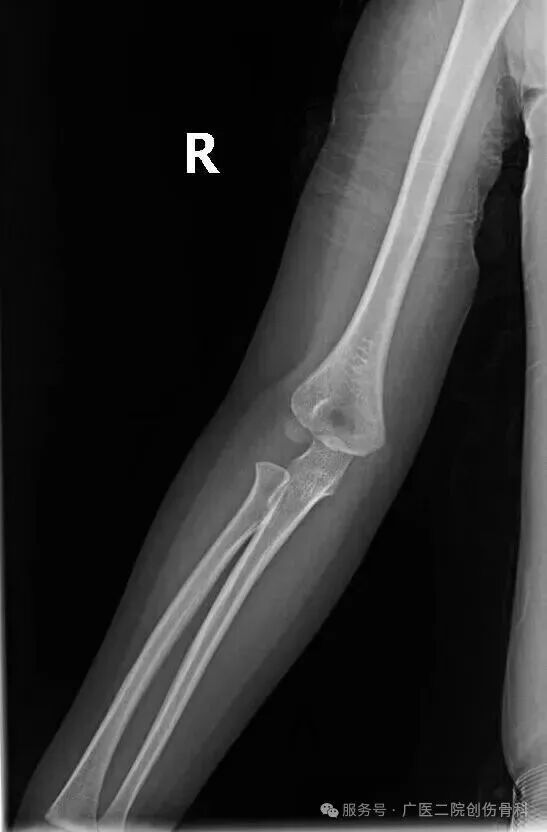

乐乐妈妈带娃来院后,胡海澜通过X光片排除骨折和脱位,结合明确的牵拉史和症状确诊为桡骨小头半脱位。

患儿X光片:肘部未见骨折及脱位征象